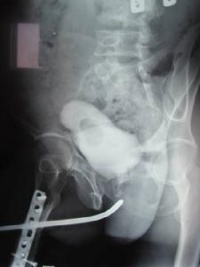

膀胱尿道造影尤适用于狭窄段口经细小或不能通过尿道探杆的病例。逆行尿道造影是由尿道外口边注入造影剂边摄侧位片,此时显示狭窄段远端较清楚。造影剂注入膀胱后,让病人一边解尿一边摄尿道侧位片(即顺行膀胱尿道造影),能较清楚地显示狭窄段近端。如患者已作膀胱造口术,可由造瘘管注入造影剂,然后在患者排尿时摄尿道侧位片。膀胱尿道造影尚可鉴别痉挛性还是器质性尿道狭窄,并可显示尿瘘。经尿道镜可以从尿道内观察到狭窄段的远端情况。

5.尿道造影:确定部位、程度、长度。